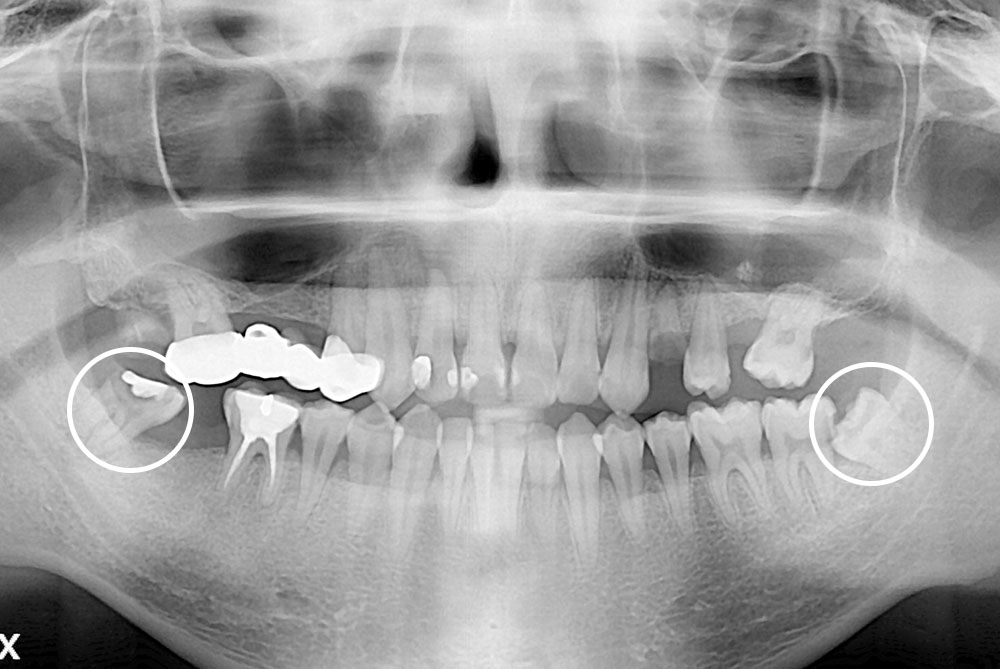

치료사례

세종치과의 진심 어린 치료는 결과로 말합니다.

실제 내원하신 환자분들의 치료 전·후 사례를 확인해보세요.

모든 치료사례 전후사진은 환자분의 동의하에 촬영되었습니다.

모든사진은 동일 환자분의 전후모습을 촬영하였으며, 사진의 밝기조절 외에 임의 수정이 없음을 알려드립니다.